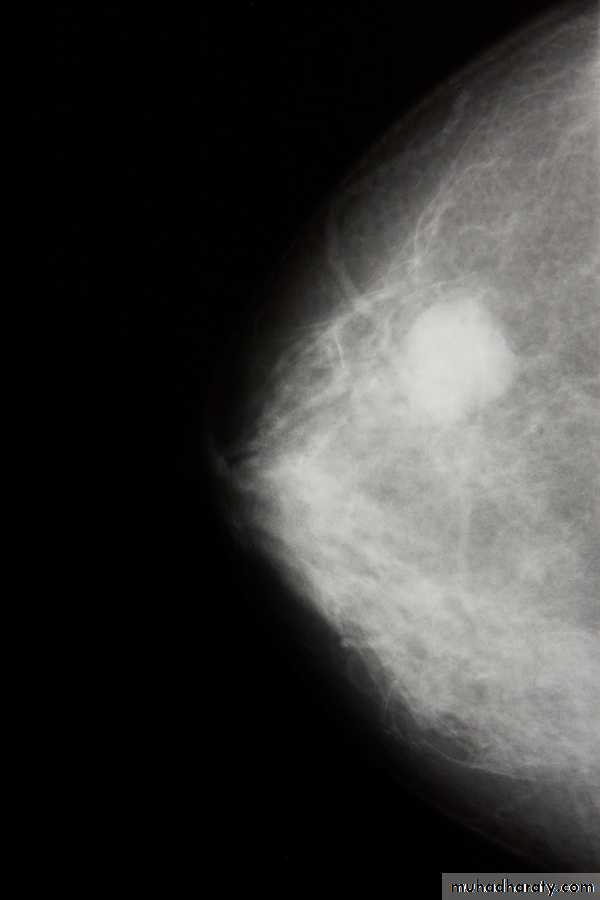

Investigations: ( 1) mammaography: soft tissue radiographs are taken by placing the breast in direct contact with ultrasensitive film and exposing it to low-voltage, high amperage x-rays. The dose of radiation is very low so it is a safe investigation. The sensitivity of this investigation increases with age as the breast becomes less dense. In total, 5% of breast cancers are missed by population –based mammographic screening programme , even in retrospect , such carcinoma are not apparent.

. Thus, a normal mammogram does not exclude the presence of carcinoma. Digital mammography is being introduced, which allow manipulation of the images and computer aided diagnosis. Tomo-mammography is also being assessed as a more sensitive diagnostic modality.

(2)ultrasound: ultrasound is particularly useful in young women with dense breasts in whom mammograms are difficult to interprets, and in distinguishing cysts from solid lesions. It also can be used to localize impalpable areas of breast pathology. It is useful as screening tool and remains operator dependent. Increasingly, ultrasound of the axillary tissue is performed when cancer is diagnosed and guided percutaneous biopsy of any suspicious glands may be performed.